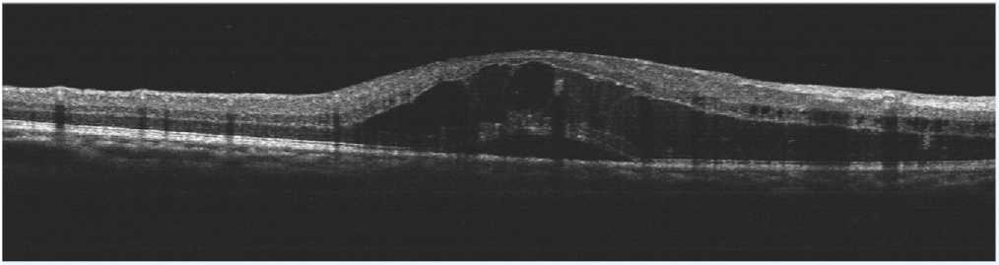

術前OCT檢查提示右眼黃斑水腫

術後OCT檢查提示(shì)右(yòu)眼黃斑神經上皮層厚度較前(qián)明顯變薄

患者劉某,58歲,因右眼視力下降伴(bàn)變形1月入院。既往有高血壓病,血糖偏高病史,左眼視物(wù)不(bú)見10餘(yú)年,經過眼科主治醫(yī)師方(fāng)霏的(de)詳細檢查及(jí)眼底造(zào)影(yǐng)檢(jiǎn)查,發現是患(huàn)上了右眼視網膜分支靜脈阻塞,右眼黃斑水腫,左眼萎縮性黃斑病變(biàn)。劉大叔入院時右眼視力僅0.1 ,需要使用一種新型的生物製劑(jì)(抗 VEGF)治(zhì)療,方霏主治醫師向患者及(jí)家屬交代病情、手術(shù)必要性及相關風險 ,在排(pái)除(chú)了手術禁忌症後,患者及家屬表示同(tóng)意手術治療。次日,方霏主治醫師在患者(zhě)表麵麻醉下進行右(yòu)眼(yǎn)玻璃體藥物注射術,術後患者(zhě)無明顯特殊不適。4周後複查,右眼黃斑水腫明顯減輕,視力由0.1提高至0.6。玻璃體腔注藥術明顯改善了患者視力,患者劉大叔表示十分滿意。